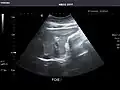

Spleen